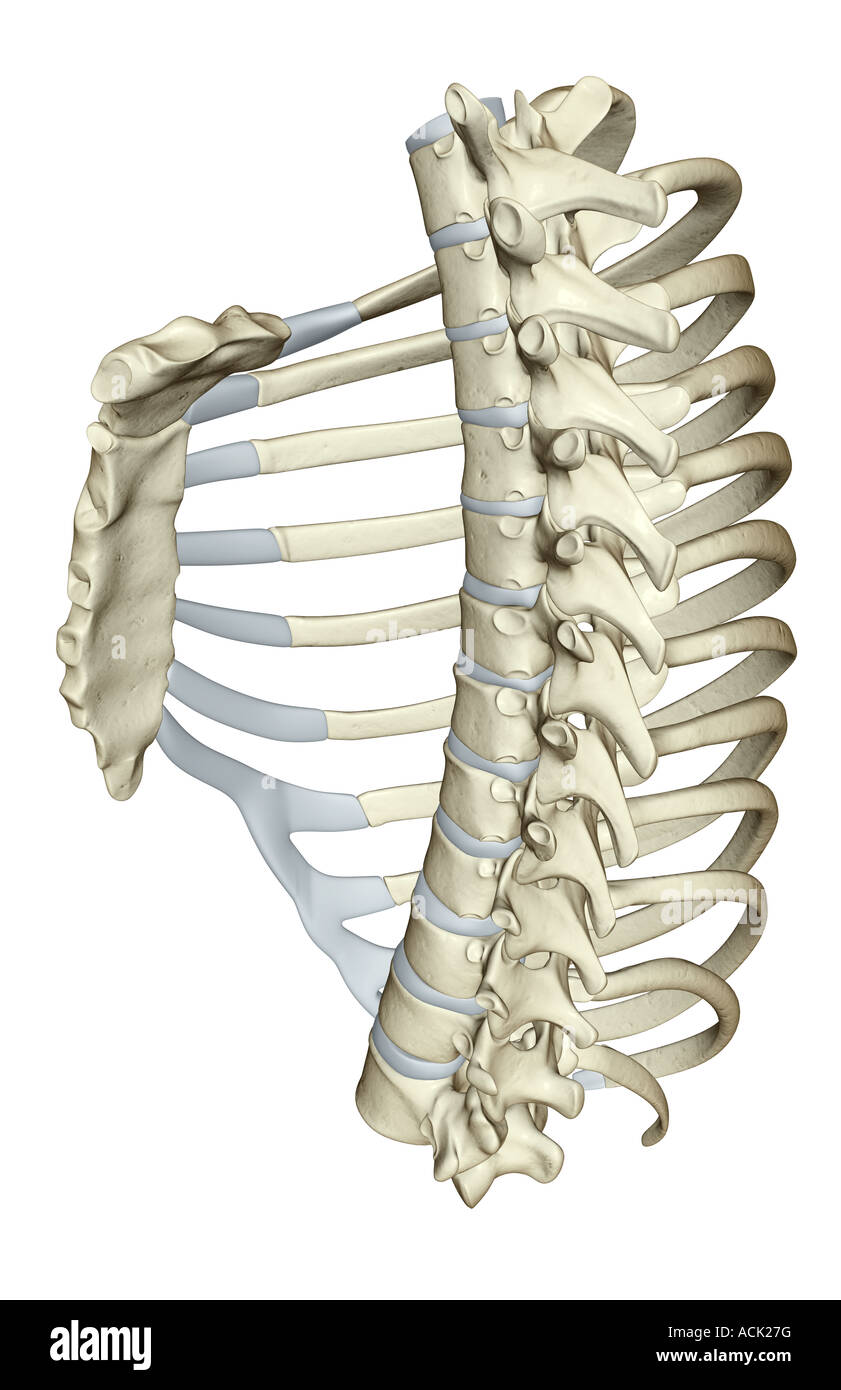

RMJ4C3NM–Questo diagramma di PSM V25 D742 illustra la struttura anatomica delle costole cervicali e il processo trasversale delle vertebre cervicali. È una rappresentazione dettagliata utilizzata nello studio dell'anatomia umana, concentrandosi sulla struttura vertebrale e sullo sviluppo delle costole.

RMPFM8F8–Una guida completa all'anatomia e alla fisiologia, che descrive dettagliatamente la struttura del torace e le variazioni nella formazione delle costole, comprese le costole sovrannumerarie e la presenza di processi trasversali. Il lavoro esplora l'analogia tra processi trasversali e costole, evidenziando le variazioni anatomiche negli esseri umani e negli animali.

RF2KEE32B–Colonna toracica T 1 anatomia ossea per concetto medico 3D Illustrazione con vista anteriore e posteriore

RF2KEE329–Colonna toracica T 11 anatomia ossea per concetto medico 3D Illustrazione con vista anteriore e posteriore

RF2KEE342–Colonna toracica T 3 anatomia ossea per concetto medico 3D Illustrazione con vista anteriore e posteriore

RF2KEE326–Colonna toracica T 4 anatomia ossea per concetto medico 3D Illustrazione con vista anteriore e posteriore

RF2KEE34K–Colonna toracica T 7 anatomia ossea per concetto medico 3D Illustrazione con vista anteriore e posteriore

RF2KEE333–Colonna toracica T 6 anatomia ossea per concetto medico 3D Illustrazione con vista anteriore e posteriore